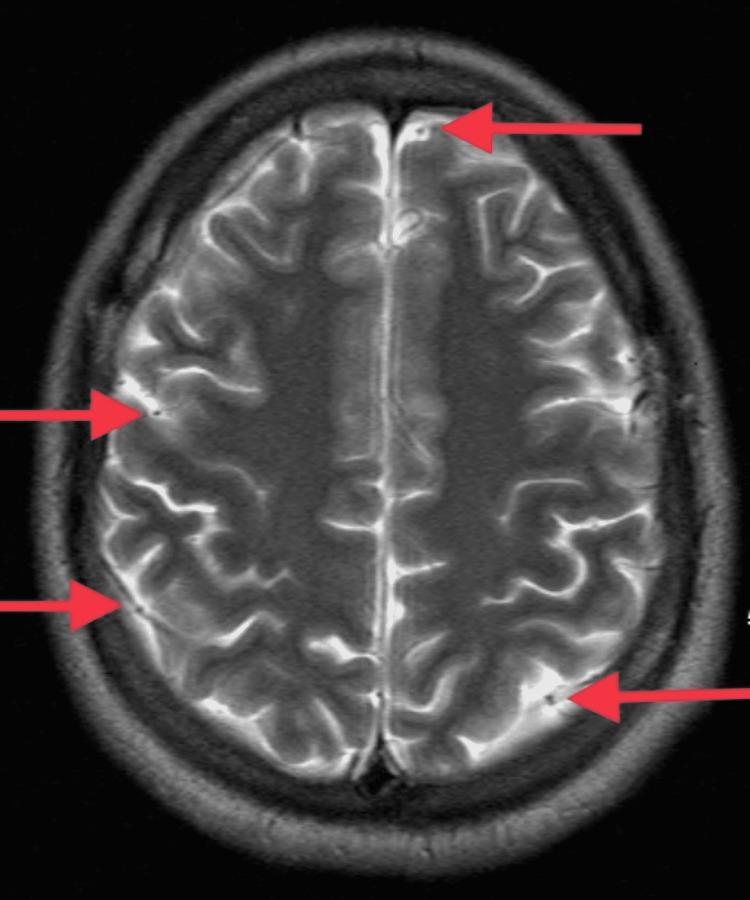

Thrombotic thrombocytopenic purpura (TTP) is a thrombotic microangiopathy (TMA) caused by decreased activity of a disintegrin and metalloproteinase with a thrombospondin type 1 motif, member 13 (ADAMTS13). Platelet-rich thrombi in small vessels lead to fragmentation of RBCs causing microangiopathic hemolytic anemia (MAHA). Therapeutic plasma exchange is life-saving and is the mainstay of the treatment of TTP. Higher dose IV steroids along with rituximab are used as an adjunct to plasma exchange. Our case report describes a 26-year-old healthy male who presented with new onset seizures and encephalopathy. Blood work demonstrated anemia, severe thrombocytopenia, elevated lactate dehydrogenase, decreased haptoglobin, and elevated creatinine, and peripheral blood smear showed marked schistocytosis indicating MAHA. Plasma exchange and high-dose steroids were started on a presumptive diagnosis of TTP. ADAMTS13 activity was undetectable and ADAMTS13 inhibitor levels were elevated. Rituximab and caplacizumab were then added. Symptoms of encephalopathy improved by day five and platelet counts started improving by day nine. After several days of plasma exchange, he showed a "clinical response" with several weeks of active treatment. The association between coronavirus disease 2019 (COVID-19) infection and the severity of TTP with multiorgan failure is not well understood yet. Although we describe a successful multimodal approach to the management of TTP, which we believe is secondary to COVID-19 infection, further research is warranted to analyze and understand the pathophysiology by which COVID-19 infection causes TTP. It would help in establishing standardized therapy in the future.

血栓性血小板减少性紫癜(TTP)是一种由具有血小板反应蛋白基序的解聚素和金属蛋白酶13(ADAMTS13)活性降低引起的血栓性微血管病(TMA)。小血管内富含血小板的血栓导致红细胞破碎,引起微血管病性溶血性贫血(MAHA)。治疗性血浆置换是挽救生命的措施,也是TTP治疗的主要方法。高剂量静脉注射类固醇联合利妥昔单抗用作血浆置换的辅助治疗。我们的病例报告描述了一名26岁的健康男性,他出现新发癫痫和脑病。血液检查显示贫血、严重血小板减少、乳酸脱氢酶升高、触珠蛋白降低和肌酐升高,外周血涂片显示明显的裂红细胞增多,提示MAHA。基于TTP的推测性诊断开始进行血浆置换和高剂量类固醇治疗。未检测到ADAMTS13活性,且ADAMTS13抑制剂水平升高。随后添加了利妥昔单抗和卡泊单抗。脑病症状在第5天有所改善,血小板计数在第9天开始改善。经过几天的血浆置换,经过数周的积极治疗,他出现了“临床反应”。2019冠状病毒病(COVID-19)感染与伴有多器官功能衰竭的TTP严重程度之间的关联尚未完全明确。尽管我们描述了一种成功的TTP多模式管理方法,我们认为这是继发于COVID-19感染,但仍需要进一步研究来分析和理解COVID-19感染导致TTP的病理生理学。这将有助于未来建立标准化治疗方案。